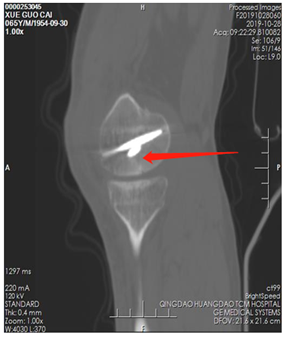

薛大叔左膝外侧有(以腓骨小头为中心)约10cmX15cm皮肤挫伤,其中间约5cmX8cm皮肤色紫,血运差;膝关节内上侧有约6cmX25cm皮肤挫伤,血运不满意 。医生为其进行了详细检查,确诊为左股骨内后髁骨折(Hoffa骨折)、左腓骨小头骨折、左膝内侧半月板损伤、左下肢挫裂伤 。

术前CT片

由于薛大叔患肢皮肤挫伤较重,若行切开手术会进一步损伤皮肤,导致皮肤坏死 。如果选择保守治疗,骨折移位,属于关节内骨折,术后会影响功能,容易并发创伤性关节炎 。骨伤一科医生考虑到薛大叔患膝关节合并半月板损伤,经评估决定采取关节镜下探查清理+半月板成形+镜下骨折内固定术 。术中仅做了1-2厘米的微小切口3处,出血少,手术进行顺利 。